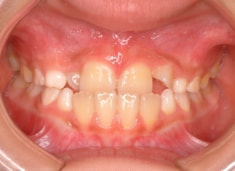

小児期ケース:反対咬合+上顎両側3番埋伏歯

(受け口+3番目の永久歯が左右両方とも埋まってしまい、はえてこない)

治療開始時